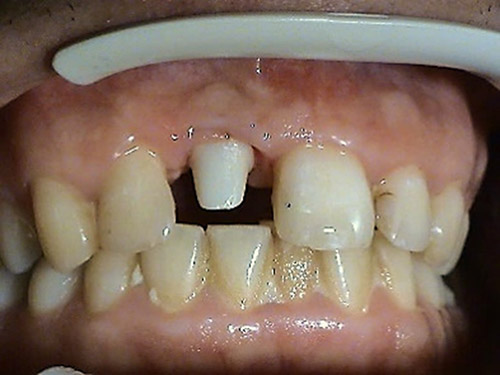

1. PHASE – implant insertion

2. PHASE – state before making immediate impressions